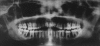

Turner's syndrome is a disorder in females characterized by the absence of all or part of a normal second sex chromosome. It is typically characterized by the combination of physical features and cytogenetics in females. Physical features include short stature, primary amenorrhea, hypogonadism, low hair line at the back of the neck, and digital anomalies. Most affected patients have a 45XO monosomy, but the presence of an abnormal chromosome or mosaicism of 45X with another cell line can also fulfill the criteria. Features seen in the oral cavity of patients diagnosed with Turner's syndrome include high palatal vault, hypoplastic mandible, prematurely erupting teeth, and orthodontic anomalies. A case of Turner's syndrome with localized aggressive periodontitis has been reported here.